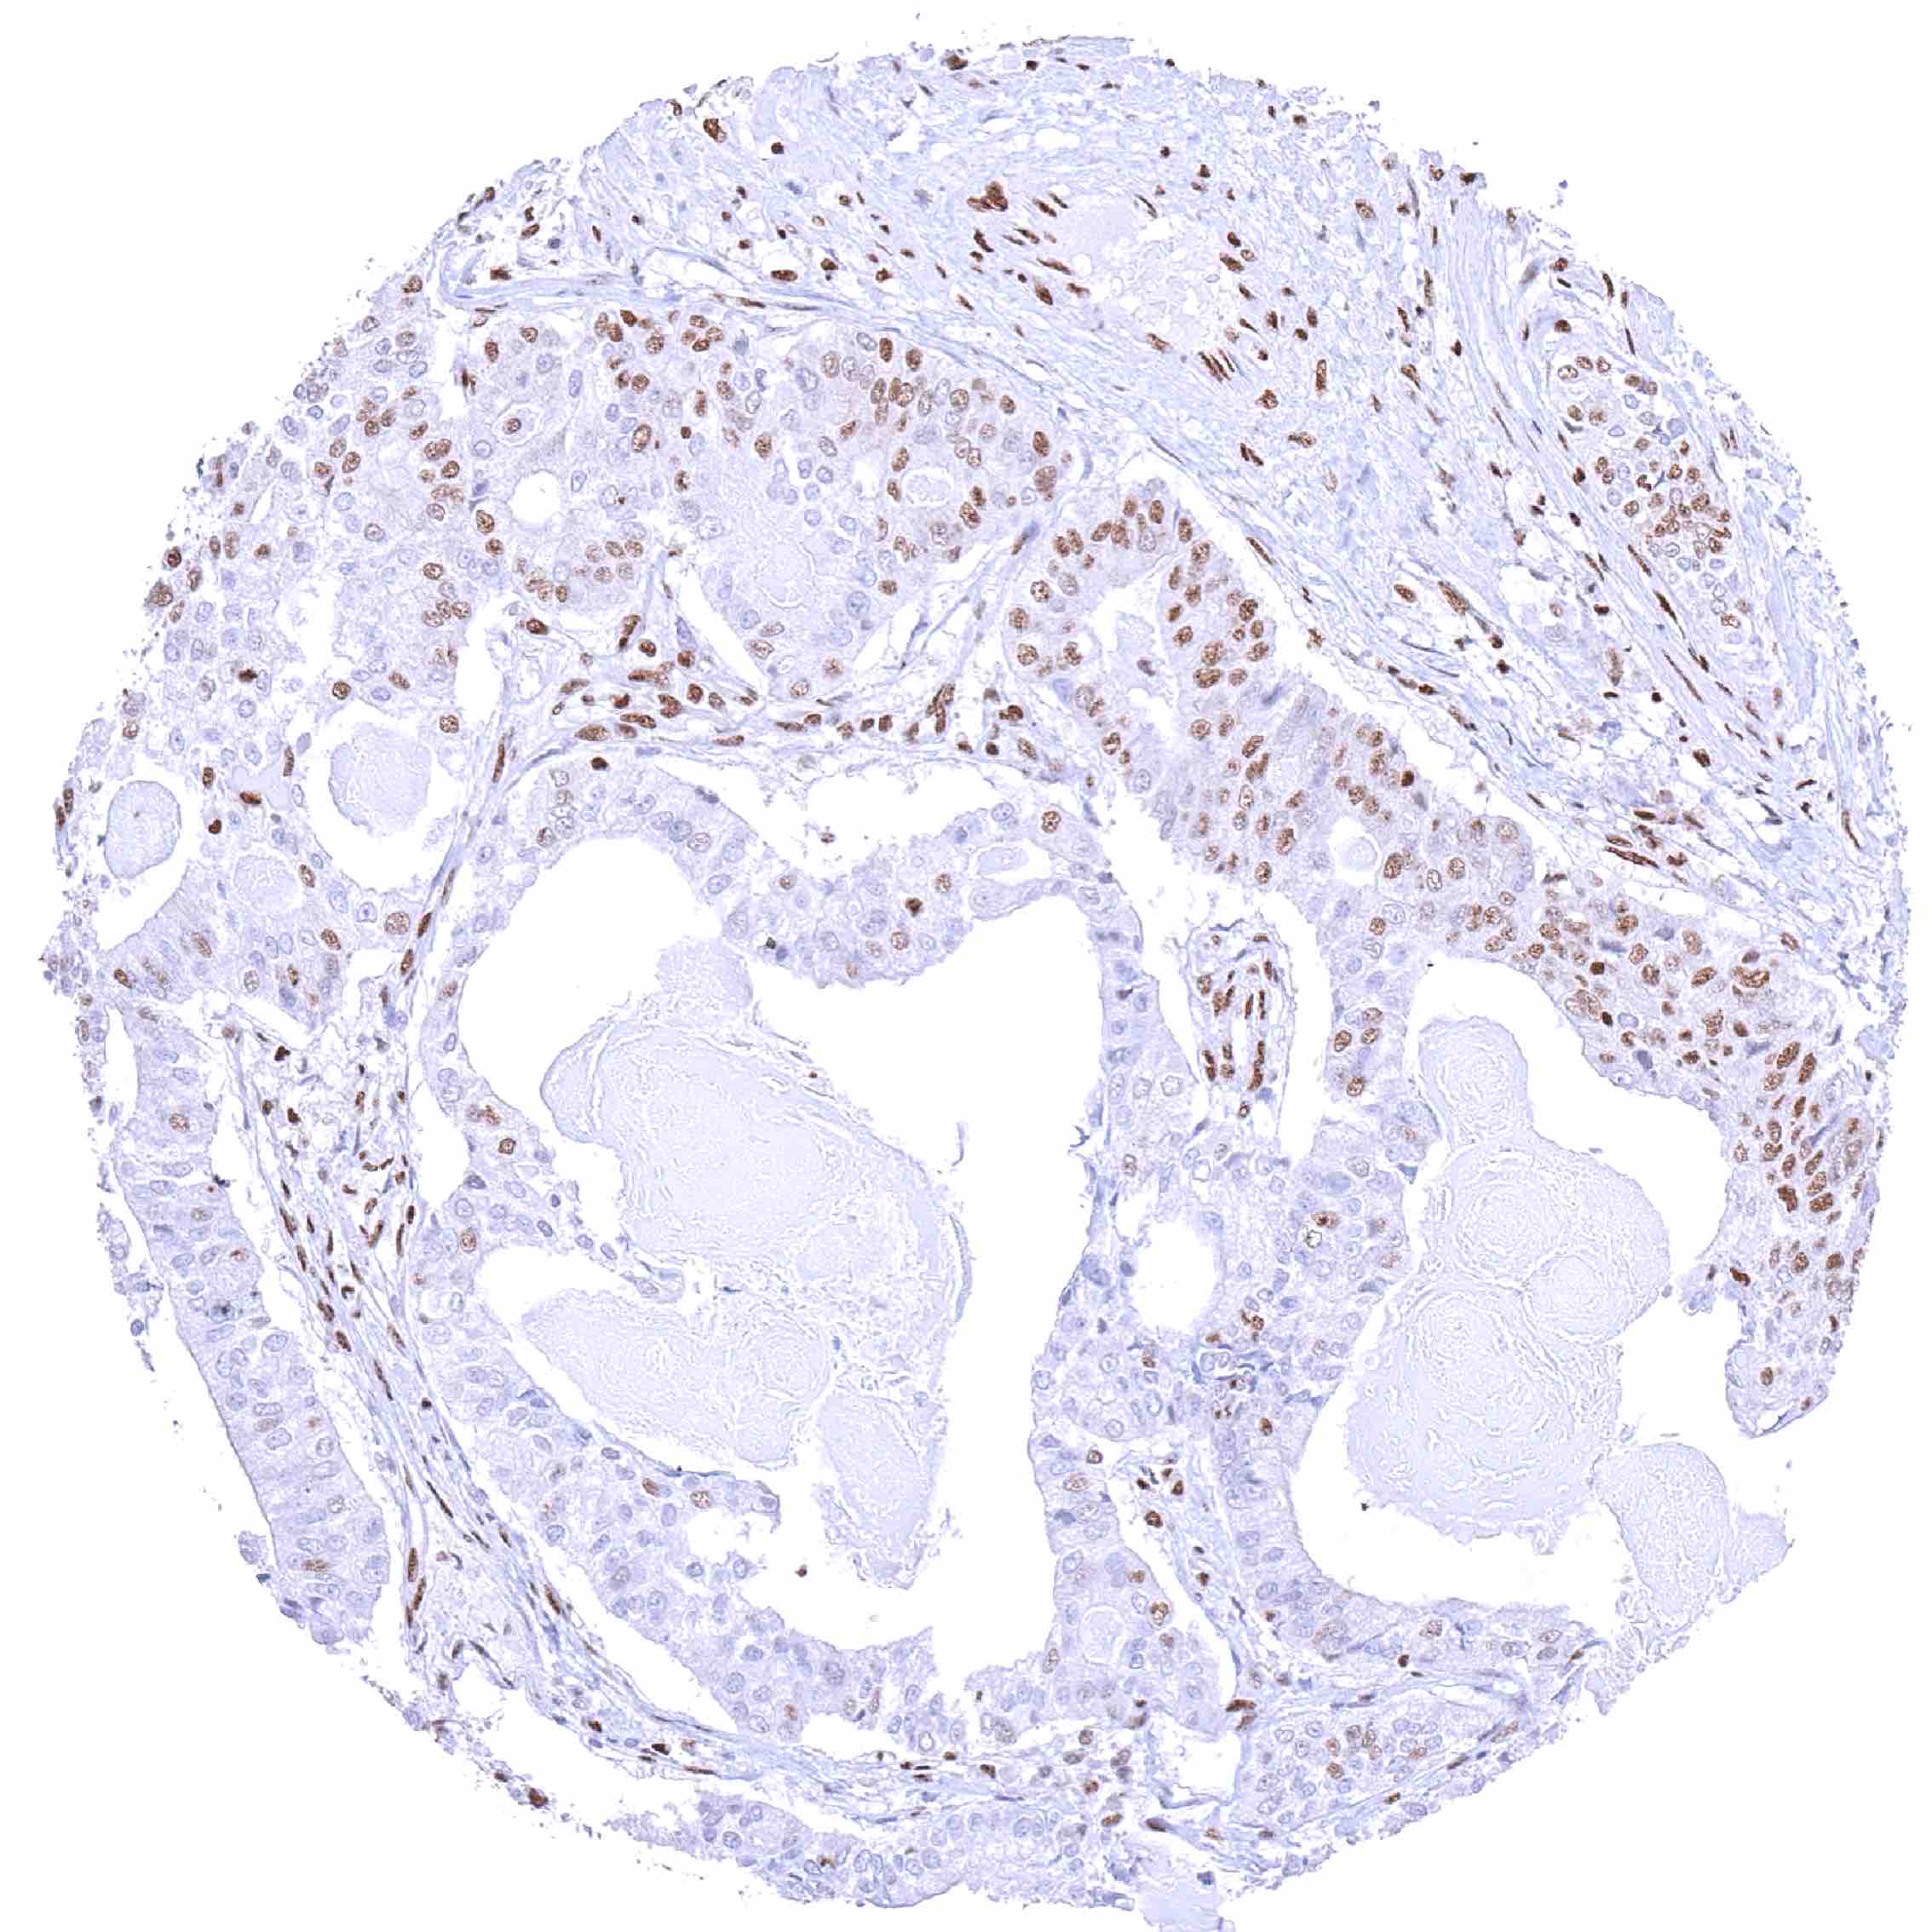

Breast – Invasive breast cancer of no special type (NST) with absent or markedly reduced BRD4 staining of most tumor cells while nuclear BRD4 staining is distinct in inflammatory cells.